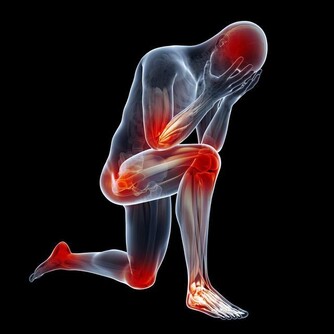

3、脾

脾臟的作用是把胃裡的精華物質加以吸收利用,是人體的過濾器!脾臟是機體最大的免疫器官,佔全身淋巴組織總量的25%,含有大量的淋巴細胞和巨嗜細胞,是機體細胞免疫和體液免疫的中心。一般說來,脾切除後,對日常生活及壽命影響不大,但近年來,有人從免疫學角度出發,認為脾切除後會使機體抵抗力降低,新陳代謝減弱,相對容易繼發感染,如呼吸道感染、腸道感染等等。

不過,脾臟不是唯一的免疫器官,術後通過一段時間的調整,機體免疫能得到一定恢復,它的部分免疫功能會被其它免疫器官替代,當然,完全恢復如常人不太可能。